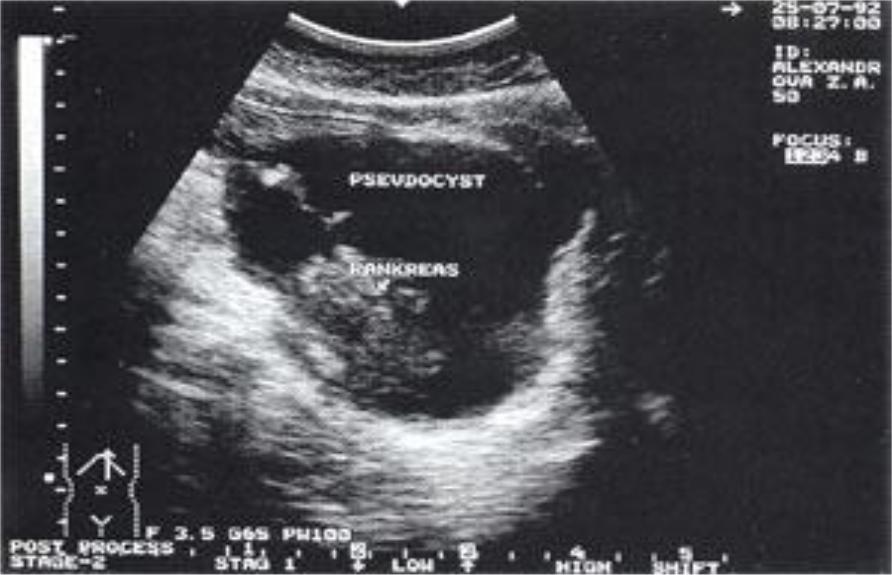

10)УЗИ: позволяет выявить наличие, характер и

протяженность патологического процесса в ПЖ увеличение и изменение плотности ПЖ, кальцинаты, псевдокисты и др.

УЗИ при хроническом панкреатите: